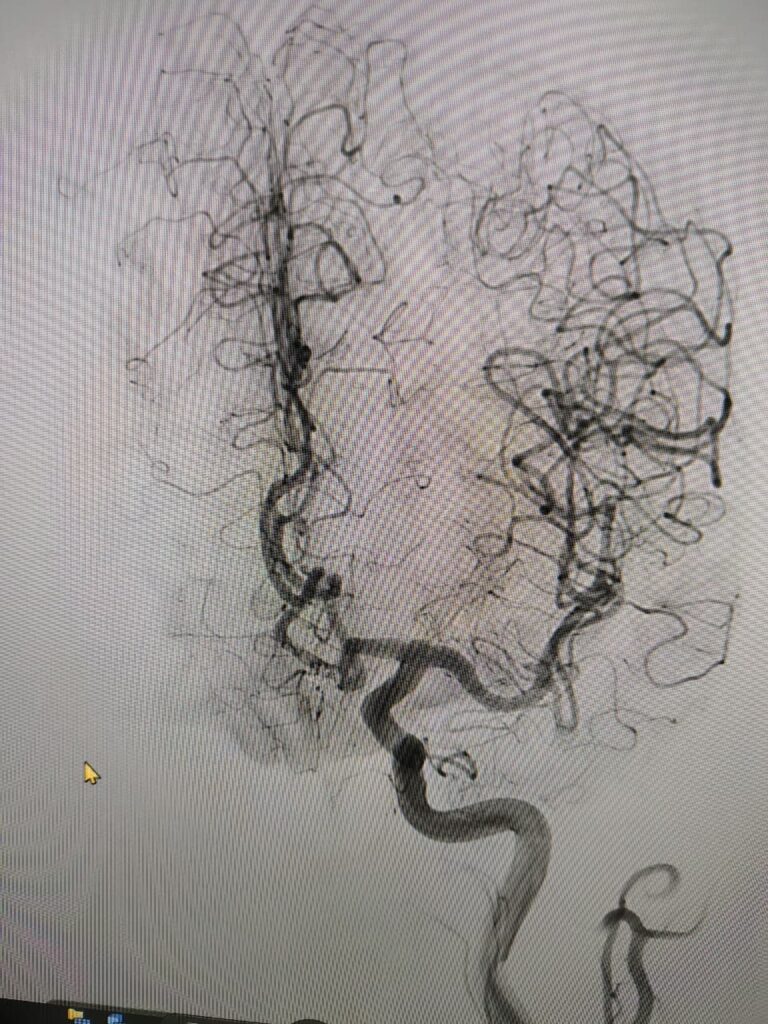

Ruptured Brain aneurysm (left ICA communicating segment wideneck aneurysm) treated with Stent Assisted Coiling.

aneurysm cannulated with microcatheter and microwire

Coiling in live case

after complete coiling and stenting

final result complete coiling and Stenting of brain aneurysm